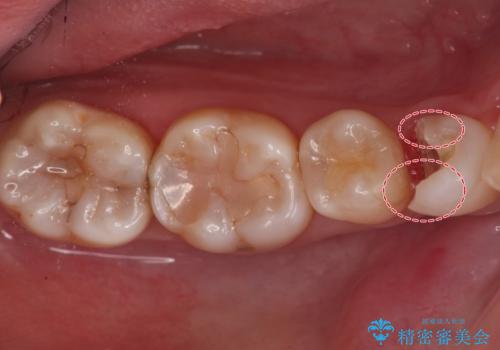

- 銀歯が目立つから白くしたいとのことで来院されました。

当初は元の詰め物と同じインレータイプでの修復予定でしたが、残った歯の厚みが薄く、今後の破折リスクを考慮しクラウンタイプでの修復処置となりました。